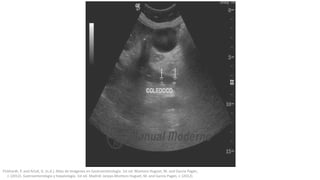

Pruebas de

imagenEcografía abdominal

Prueba de elección para iniciar la investigación de un paciente

con sospecha de CDL, aunque sólo llegan a visualizarse en el

50% de los casos. Sin embargo, su sensibilidad para detectar la

dilatación del colédoco (superior a 6 mm en pacientes con

vesícula y a 8 mm en colecistectomizados) es de un 75%

aproximadamente.

-En individuos con cálculos biliares, ictericia y dolor biliar, un colédoco

dilatado en la ecografía sugiere con firmeza cálculos en el colédoco-